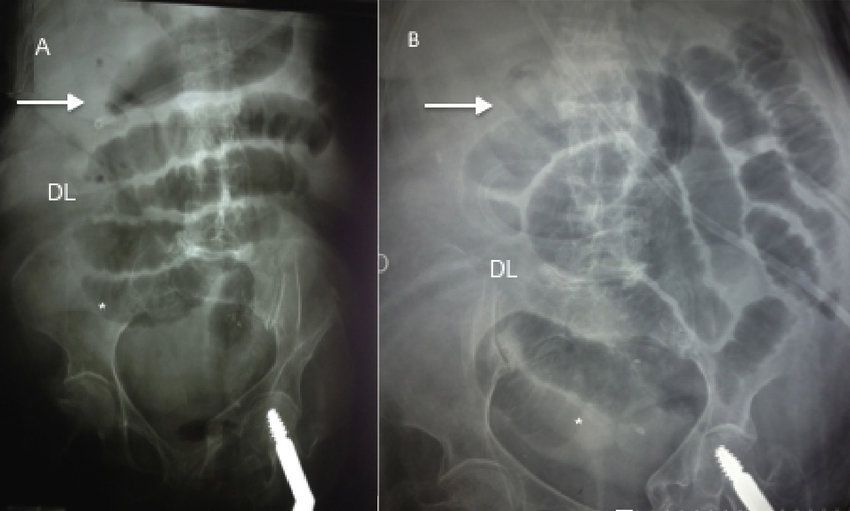

Rigler triad is a triad of radiological findings in case of gallstone ileus. These findings are: 1. pneumobilia 2. ectopic calcified gallstone 3. small bowel obstruction Reference: https://radiopaedia.org/articles/rigler-triad-gallstone-ileus Image via: https://www.researchgate.net/publication/317329758_Gallstone_ileus_An_overview_of_the_literature/figures?lo=1&utm_source=google&utm_medium=organic